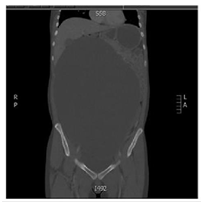

24 year old female patient who attends to overall control, at the time of referred was found asymptomatic in history but I indicated that her mother had died of liver sarcoma no other antecedent family, personal or surgical, referred menarche at 13 years, with regular menstrual cycles without recent changes from cycle frequency or amount of menstrual bleeding, condom use as a method of family planning for 6 years, when no gestational history, clinical examination only increased abdominal girth positive ascetic wave was evident, no changes in abdominal surface vasculature, masses or palpable organ enlargement were evident, no abdominal pain or discoloration of skin or mucosa, thus possible ascites was considered establish and given rise to this initial studies to study origin of ascites were requested. During the next control, no changes compared to previous clinical examination were evident in paraclinical transaminases and bilirubin. the reports in normal parameters, hematology and normal clotting times, quantitative BHCG<0.10mIU/mL (negative) and abdomen total ultrasound showed limited by the large amount of free fluid in the abdominal cavity, with decreased bilateral renal size and dilated right renal pelvis, study no proper evaluation of abdominal organs was achieved by a free liquid, the above clinical suspicion gave gynecopathologists possible neoplasic whereby extension tests were completed including abdominal tomography contrast to study possible neoplastic lesions. For the next control in clinical examinations showed a normal peripheral blood smear, differential protein and globulin normal blood, a 0.90mg/dl for CKD-EPI GFR 88.3mL/min/1.73m2, HIV testing and syphilis serology negative, alpha-fetoprotein 0.9ng/dl (negative), carcinoembryonic antigen 1.32ng/ml (negative), CA 07.16 19.9 IU/ml (negative), CA 125 8.98UI/ml (negative) and the CT abdomen which was evident great mass apparently left adnexal cystic density occupies the whole of the abdominal cavity with mass effect on abdominal organs. Figure 1 & Figure 2 with compressive effect on the right proximal ureter setting moderate hydronephrosis, Figure 3. Therefore requested assessment by the Gynecologic Oncology Service, which program for exploratory laparotomy. Day May 19, 2018 was performed in the patient exploratory laparotomy, where a large cystic mass dependent left annex of about 35cm in major diameter was found. The colour pearlescent compromising left ovary, compression and abdominopelvic displacement organs which tumor resection of the left ovary, omentectomy and appendectomy was performed, samples were sent to pathology for initial study by freezing and subsequent histopathology block. The pathology report indicated: cyst benign ovarian serous papillary cystadenoma consistent, residual ovarian parenchyma with simple epithelial follicular cysts and inclusion in the other samples not suggestive evidence for histopathological changes. Neoplasms, acute or chronic conditions; cytology extracted cyst fluid was negative for malignancy. The patient is discharged after two days without, currently present complications of surgical procedure in outpatient clinical follow by the mass of secondary ovarian origin hydronephrosis.

Figure 2 Sagittal section showing evidence of left ovarian dependent mass.